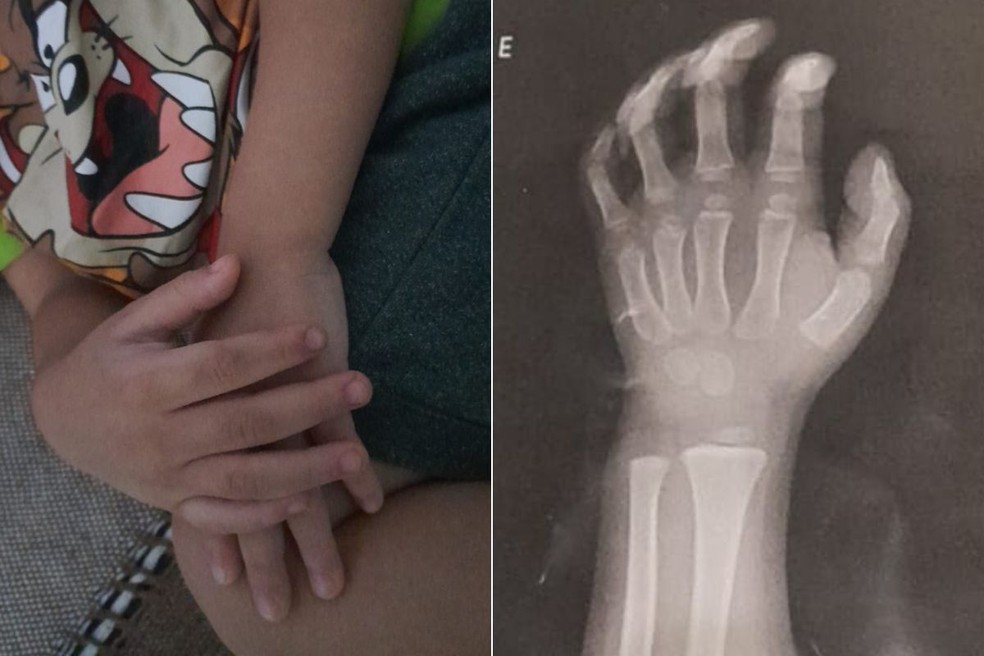

O caso ocorreu no Núcleo de Educação Infantil Conveniado (Neic) Espírita Cristã Maria de Nazaré. A avó do menino relatou que a família foi chamada à creche no dia 28, pois a criança reclamava de dores no braço. Após atendimento na UPA Enseada e, posteriormente, na UPA da Rodoviária, um exame de raio-x constatou a luxação.

A avó relatou que o neto revelou que a professora havia machucado seu braço. Imagens das câmeras de monitoramento mostram a professora pegando um livro do colo do menino e, após ele jogar um brinquedo no chão, segurando-o bruscamente pelo braço, arrastando-o até o meio da sala e o colocando de castigo.